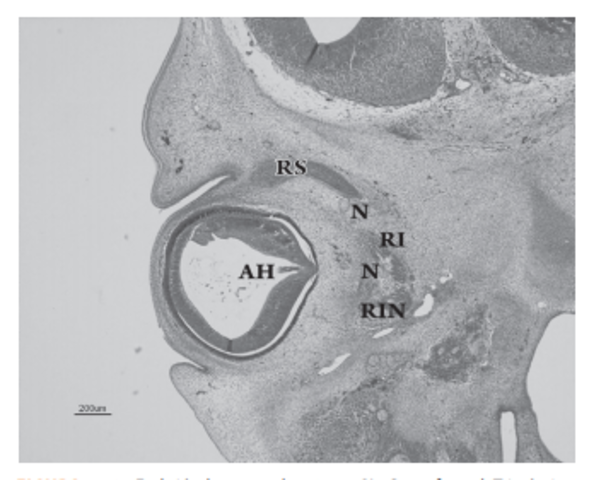

La vesícula óptica está relacionada con la formación de la placoda cristaliniana, ésta se invagina, constituyendo la vesícula cristaliniana. Al mismo tiempo, laporción distal e inferior de la vesícula óptica se deprime de forma gradual para formar una invaginación con dos capas, interna y externa, denominada cúpula óptica

Esta invaginación recorre longitudinalmente el pedículo óptico formando una hendidura conocida como hendidura embrionaria (fisura coroidea).

DESARROLLO DEL NERVIO ÓPTICO

- Los axones de las células ganglionares de la retina neurosensorial crecen hacia el pedículo o tallo óptico. De esta manera, la cavidad del tallo se va obliterando. La aparición de los axones en la futura papila se observa en embriones de 16 mm de longitud GL; 6,5 semanas de desarrollo, 44 días. Las células del pedículo óptico rodean cranealmente a estas fibras y a la arteria hialoidea